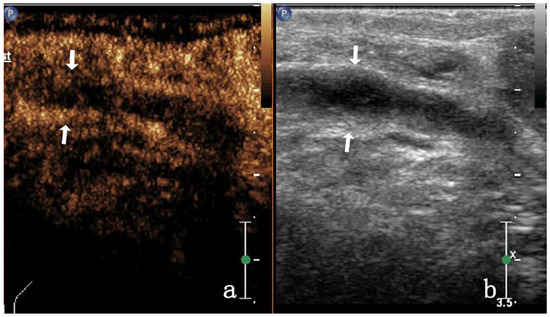

| Heterogeneous enhancement | septal enhancement | 4/17 (23.52%) | 0 | ||

| non-enhancement | 3/17 (17.64%) | 0 | |||

| Low enhancement | 5/17 (29.41%) | 0 | |||

| Equal enhancement | 4/17 (23.52%) | 0 | |||

| Noncentripetal enhancement | 17/17 (100%) | 12/28 (42.85%) | |||